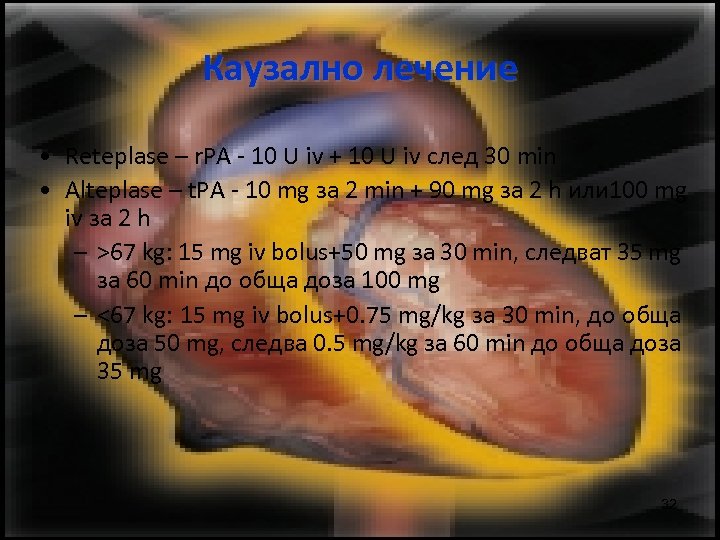

Каузално лечение • Reteplase – r. PA - 10 U iv + 10 U iv след 30 min • Alteplase – t. PA - 10 mg за 2 min + 90 mg за 2 h или 100 mg iv за 2 h – >67 kg: 15 mg iv bolus+50 mg за 30 min, следват 35 mg за 60 min до обща доза 100 mg – <67 kg: 15 mg iv bolus+0. 75 mg/kg за 30 min, до обща доза 50 mg, следва 0. 5 mg/kg за 60 min до обща доза 35 mg 32

Каузално лечение • Streptase - 2000 U/kg за 10 min+4000 U/kg/h for 24 h iv • Urokinase - 4400 U/kg+4400 U/h за 12 h • Enoxaparine – 1. 5 -2 mg/kg/d sc • Heparine – 100 -120 UI/kg/d до INR 1. 5 -2. 5 х • Венозен филтър • AVK – 3 -6 седмици INR (2 -2. 5) 33